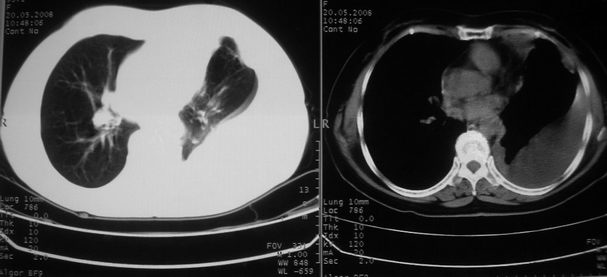

以下是引用w_jianhua在2008-5-22 12:59:00的发言:[br]1.左肺上叶肺癌并左侧胸腔积液可能性大。2不除外支气管内膜结核并包裹性胸腔积液,建议支气管镜检3.左肺下叶肺大泡,肺气肿